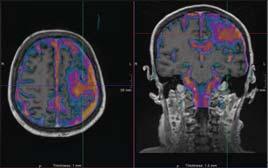

The CIAMA project by Hamilton hospitals and schools will enable trainees, researchers and clinicians to share a leading-edge MRI Pictured (l to r): Wendy Lawson, Mohawk College; Paul O’Byrne, McMaster U; Ron McKerlie, Mohawk College; Rob MacIsaac, HHS; Sylvia Jones, Deputy Premier; Donna Skelly, MPP; David Farrar, McMaster U; Dr. Julian Dobranowski, McMaster U; John Aldis, St Joseph’s. SEE STORY ON PAGE 12

HAMILTON, ONT. – Mohawk College and McMaster University have announced the opening of a new facility for educational training, imaging research and magnetic resonance imaging (MRI) that promises to cut wait times and improve patient experience.

The Centre for Integrated and Advanced Medical Imaging (CIAMI), provides a space where education, clinical care, and research intersect through collaborative and unique models of care and approaches to training that have not been done before in Ontario.

Located at the Mohawk-McMaster Institute of Applied Health Sciences building on McMaster’s main campus, the facility includes a newly installed advanced MRI unit, the second of its kind in Canada.

CIAMI provides a revolutionary approach to cutting wait times and could double the speed of service for patients needing MRI scans. Currently, the average for MRI scans is 1.54 patients per hour in Ontario, but early CIAMI data from a pilot at St. Joseph’s suggests that could be improved.

CIAMI enables a new model of training with a living lab for interdisciplinary

The centre will also be the site for continuing research, with access to innovative technologies and the use of artificial intelligence (AI) to enable cutting-edge discoveries. CIAMI brings technology and healthcare together in Hamilton to propel advancements in imaging research.

“We have a backlog of patients waiting for MRI scans in our region, we are

facing a health human resource crisis in Ontario, we have challenges in meeting the imaging needs of our hospital in-patients and our researchers need access to equipment that isn’t competing with clinical needs,” said Julian Dobranowski, professor and chair of the Department of Medical Imaging at McMaster and an adjunct professor at Mohawk College.

“CIAMI provides an innovative solution to all of these issues. We are excited to validate this new model of care to en-

This unique model, combining MRI research, training and clinical care, hasn’t been used in Ontario before now.